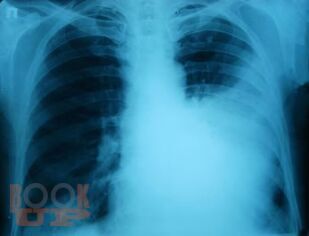

В части I представлен учебный материал по темам «Пневмония» и «Острые инфекционные деструкции легких». По каждой теме изложены современные научные данные по этиологии, патогенезе, классификации, клинике, методах диагностики, лечения и профилактики заболеваний, способствующие формированию у обучающихся общепрофессиональных компетенций ОПК-4, ОПК-5, ОПК-7 и профессиональных компетенций ПК-5, ПК-6, ПК-8, ПК-10, ПК-11. Для самоконтроля обучающимися сформированности компетенций предложены тестовые задания и ситуационные задачи с эталонами ответов, составленные авторами по учебному материалу с учетом индикаторов достижения компетенций.